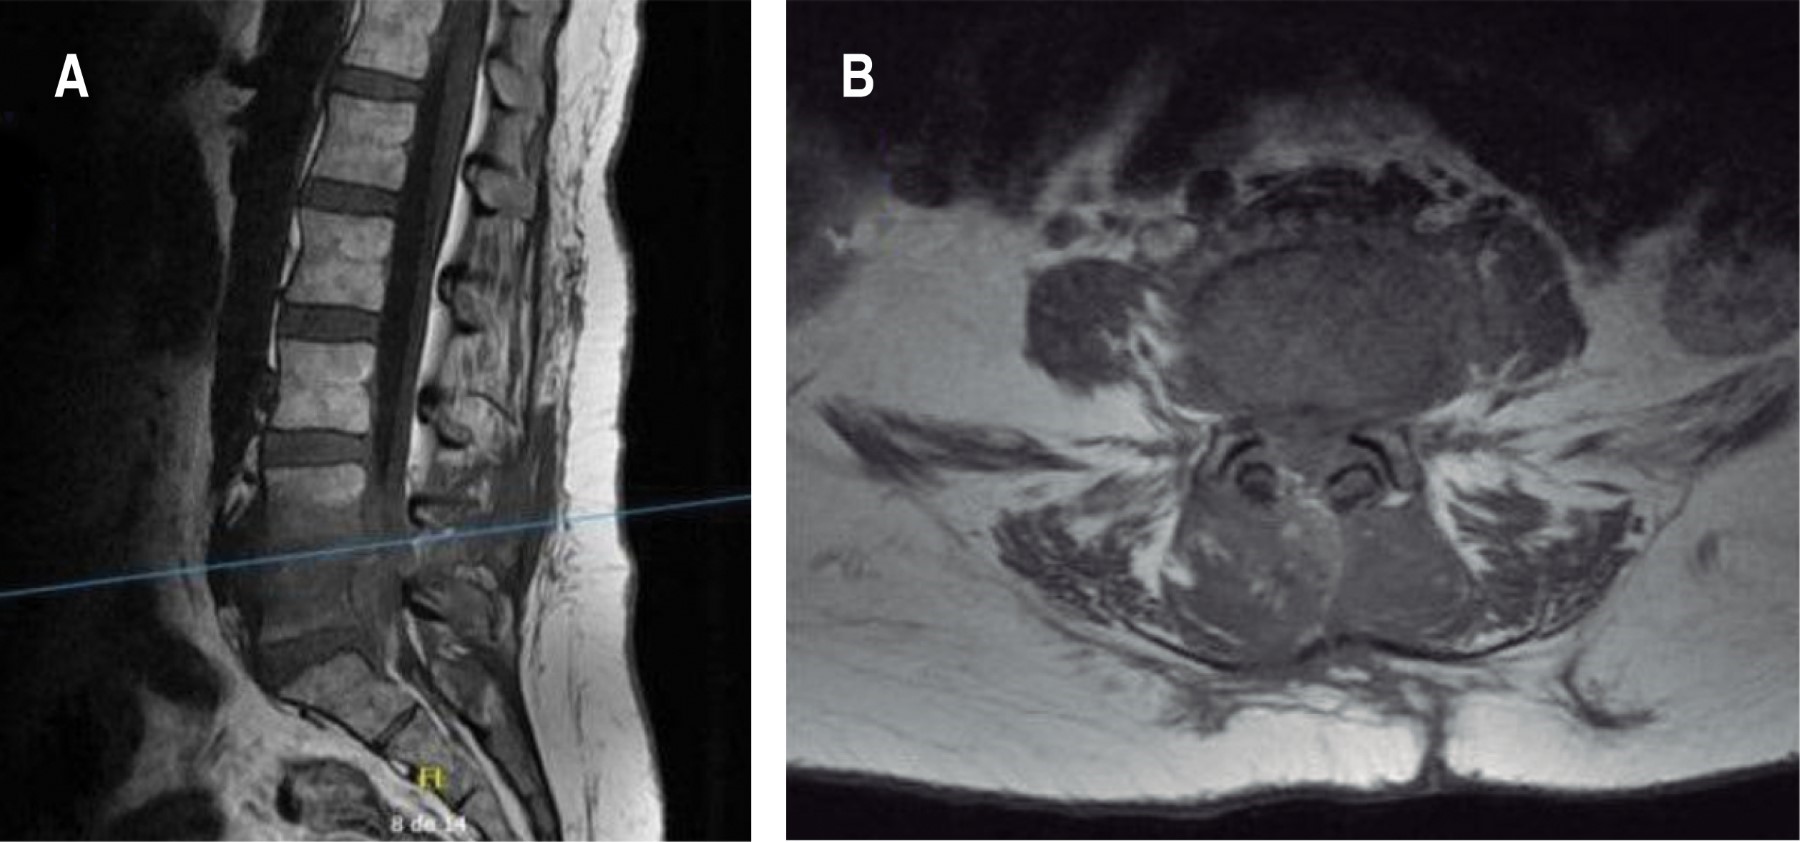

Figura 1